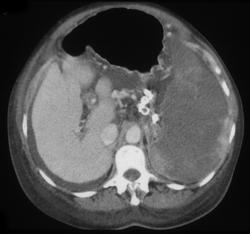

Splenic Infarction Due to Pancreatic Cancer